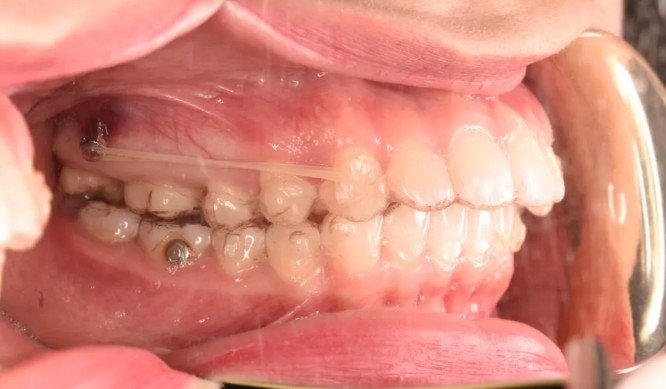

妹紙做隱適美磨牙后推打骨釘?shù)恼澜?jīng)歷,沒想到效果挺不錯

隱適美牙博士口腔隱形矯正牙齒發(fā)布時間: 2020-02-12

為了不拔牙,我選擇了在溫州牙博士口腔做隱適美磨牙后推打支抗釘矯正,沒想到真如醫(yī)生所說,效果挺不錯的!來說說我的整牙經(jīng)歷吧~